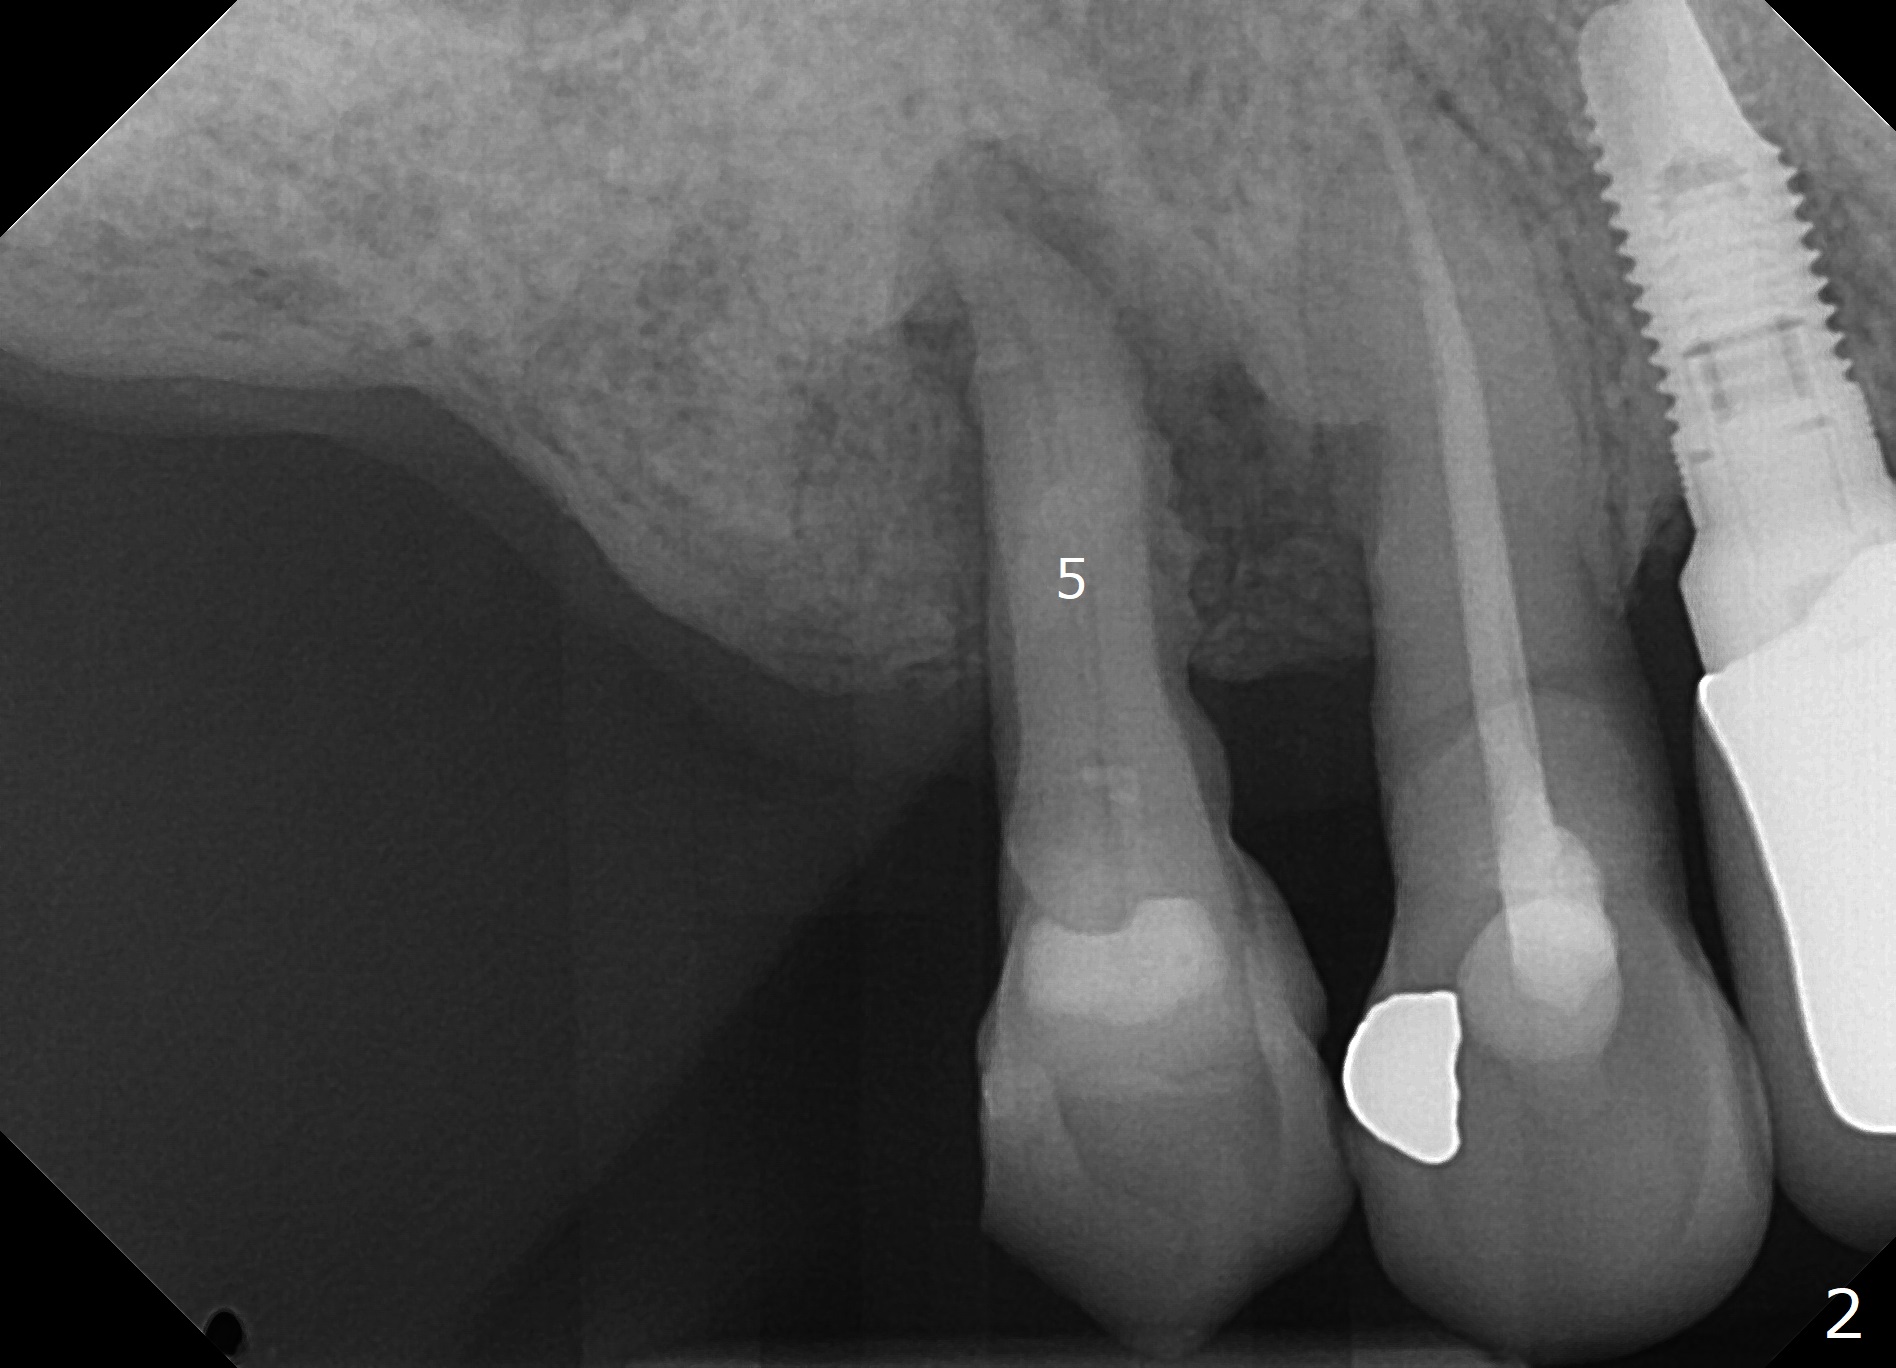

A 70-year-old woman with multiple restoration and several missing teeth (Fig.1) has sensitivity to sweet and cold at #4 (Fig.2). There is moderate gingival recession, slightly more severe buccal. CT will be taken to determine whether immediate implant is indicated. The buccal plate is most likely missing. If the vein is too thin for PRF, GEM21S will be used with possible GEM Cap RCM.